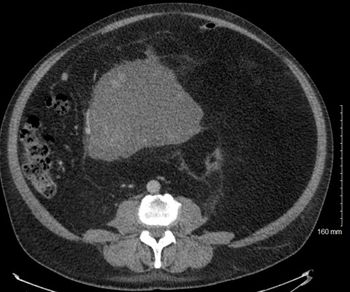

A 51-year-old man noticed abdominal swelling and distention with intermittent abdominal pain, early satiety, and decreased appetite over the past several months. A computed tomography scan of the abdomen is performed. What's your diagnosis?

Retroperitoneal sarcoma is a rare tumor whose diagnosis and management can be challenging and for which management requires a multidisciplinary team.

Sarcomas are relatively rare malignant tumors that arise from mesenchymal cells and therefore encompass a variety of histologies and can occur in any anatomic compartment. The incidence of sarcoma is estimated at 1% of all new cancer diagnoses in the United States annually. Approximately 15% of soft tissue sarcomas occur in the retroperitoneum, with about 1600 new retroperitoneal sarcoma cases diagnosed in the United States each year.